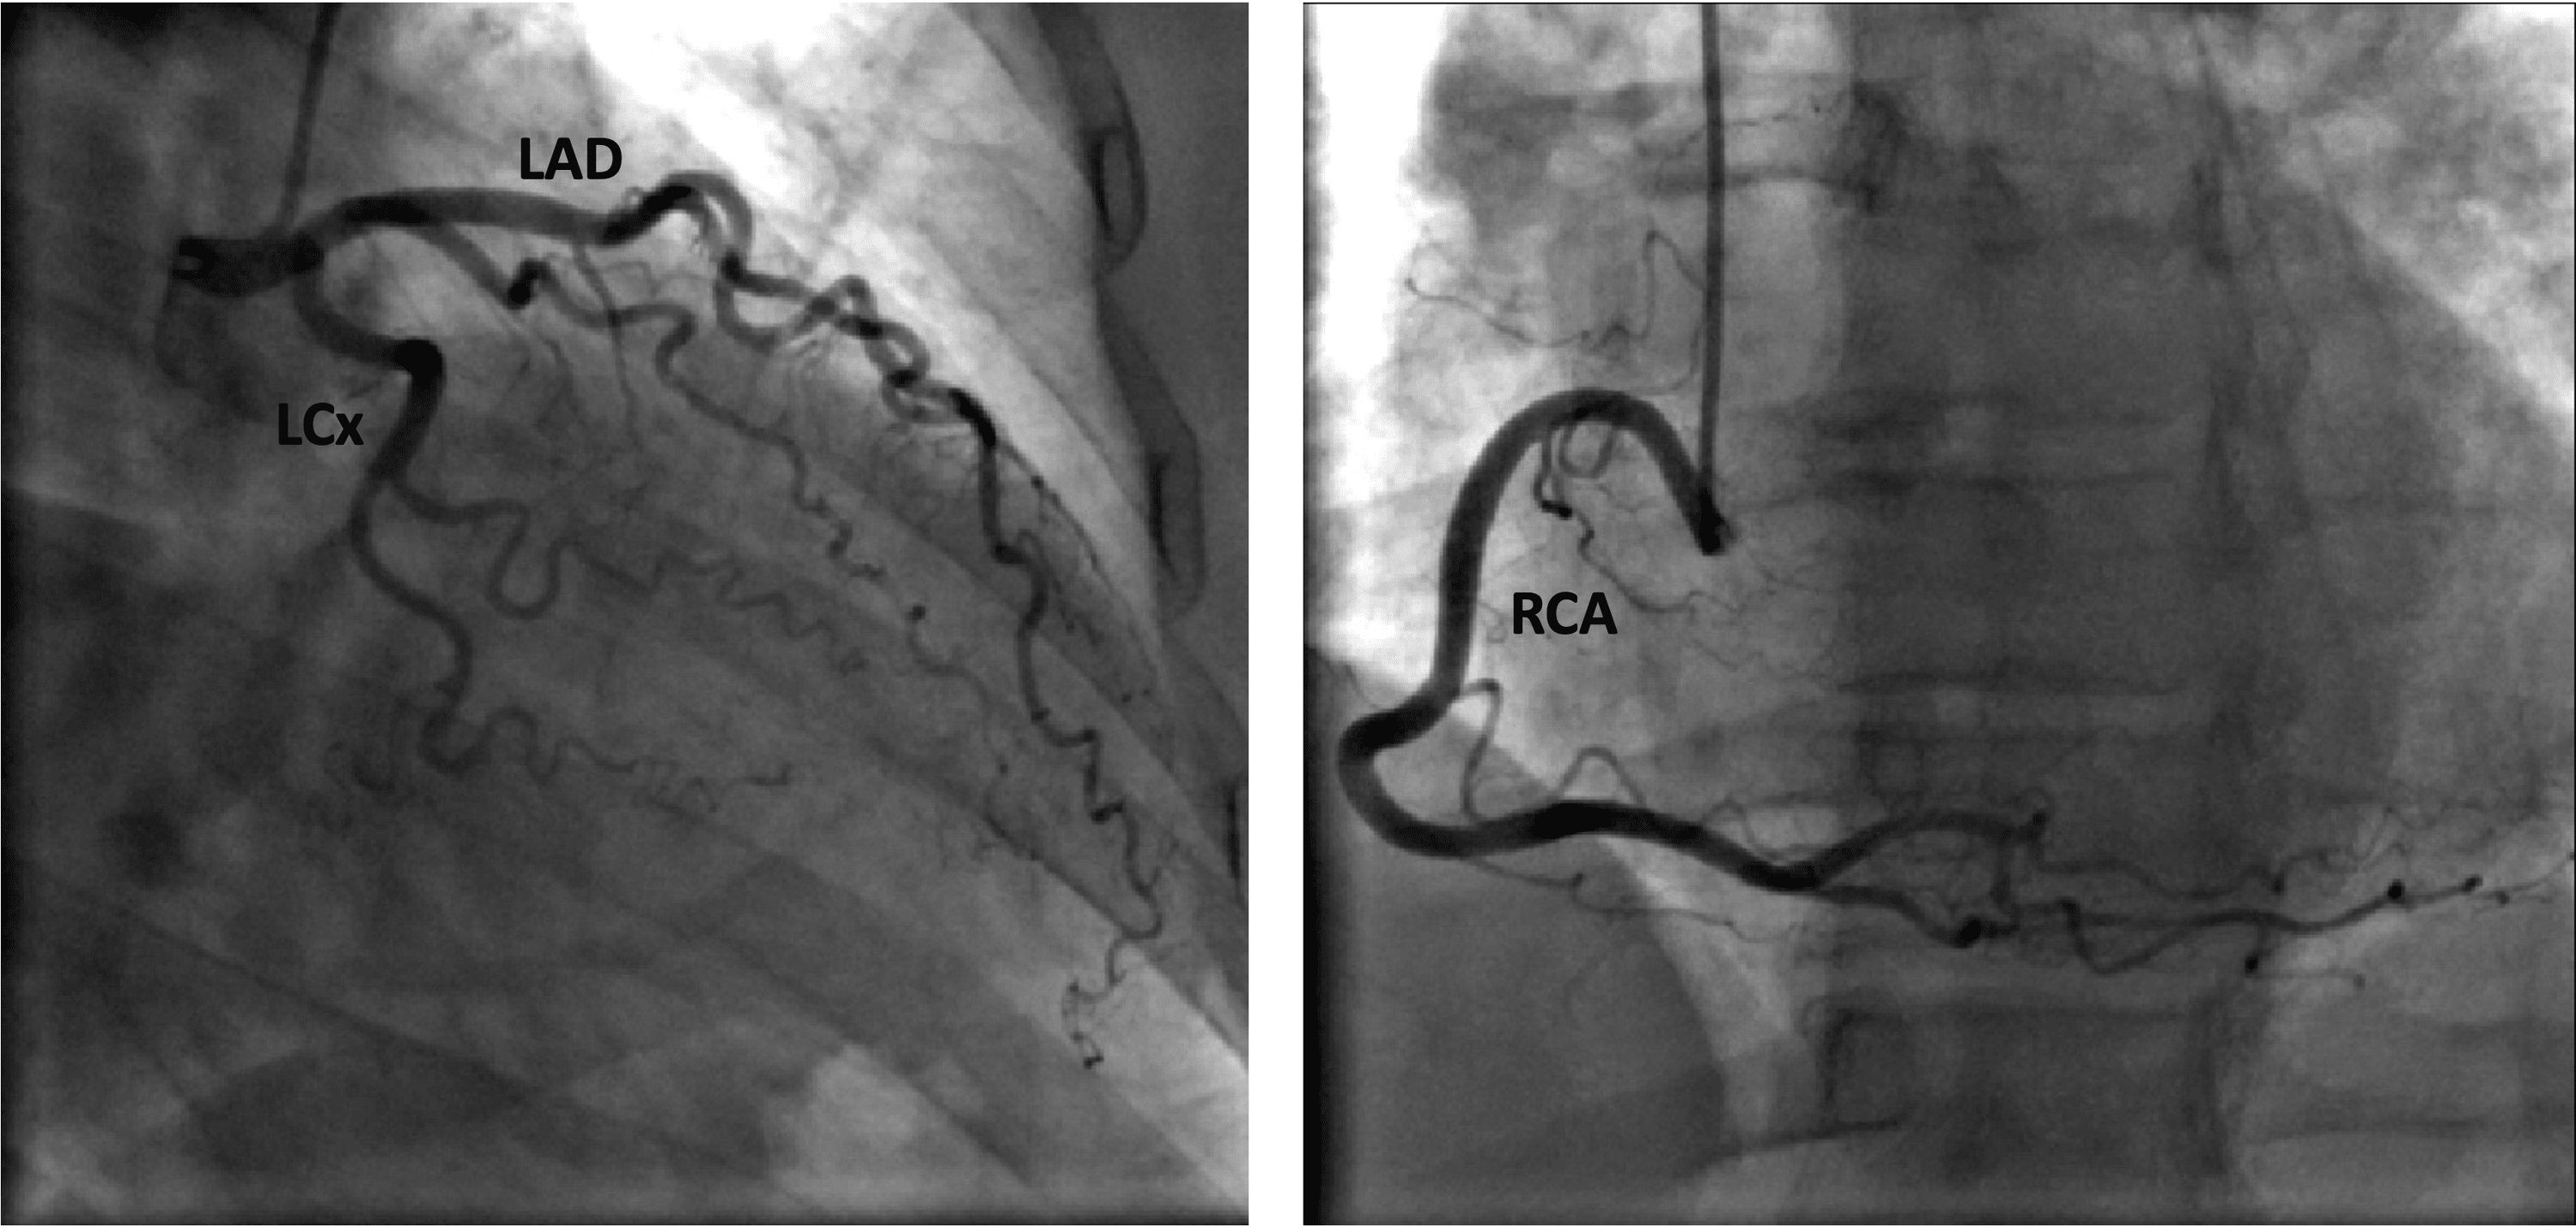

From www.cureus.com

Cureus Positive Regadenoson Stress Test in a Patient on Phentermine With Normal Coronaries Heart Catheterization Stress Test Take a tiny bit of muscle from your. A main objective of stress testing is to assess the functional or physiological consequences of anatomic coronary artery. Current us stable ischemic heart disease guidelines favor noninvasive functional testing for myocardial ischemia in most. Cardiac catheterization is used to: Cardiac catheterization (cardiac cath or heart cath) is a procedure to examine how. Heart Catheterization Stress Test.

Cureus Negative Stress Test Is Not Always Negative Revisiting the Clinical Implications of Heart Catheterization Stress Test If a screening exam, such as an electrocardiogram (ecg) or stress test, suggests there may be a heart condition that needs to be explored further, your healthcare provider may order a cardiac. Current us stable ischemic heart disease guidelines favor noninvasive functional testing for myocardial ischemia in most. Cardiac catheterization is most often performed after completion of a history and. Heart Catheterization Stress Test.